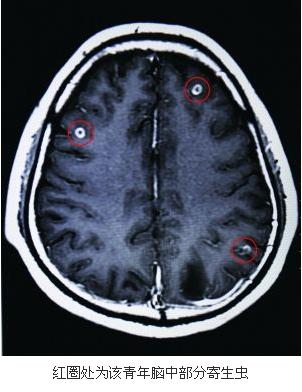

「ブタの生き血」が大好物の男性、脳内から寄生虫19匹発見―中国紙

中国紙・貴陽晩報によると、めまいと視力低下に悩む青年の大脳には、なんと19匹の寄生虫がいた。彼の大好物のブタの生き血が原因だという。